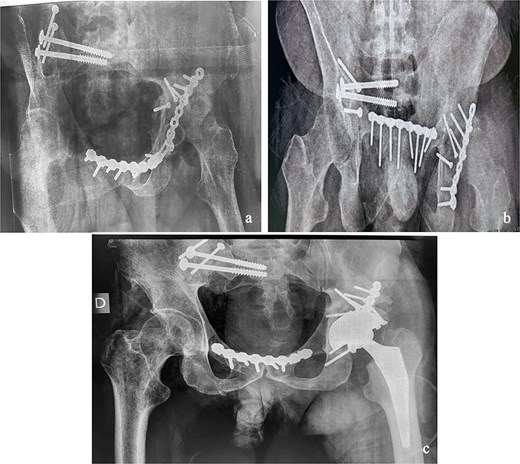

At the 10-month follow-up, the patient showed signs of left hip osteoarthritis with functional deterioration, for which a total ceramic-on-ceramic hip arthroplasty was performed, using a screw-fixed structural graft at the acetabulum (Fig. 3). At the final follow-up, 36 months postoperatively, the patient was walking unaided with the use of an anti-equinus splint on the left foot. The HHS was 85 and Majeed score was 86 [6, 7]. X-rays showed complete bone healing of all fractures and the acetabular graft. It should be noted that, during follow-up, the patient had a right femoral fracture that was successfully treated with a gamma nail (Fig. 4). Written informed consent were obtained from the patient.

(a and b) Inlet and obturator oblique views showing a left hip osteoarthritis with subluxation of the femoral head. (c) Anteroposterior pelvic X-ray: left total hip arthroplasty, acetabular bone reconstruction with a screwed structural bone graft.